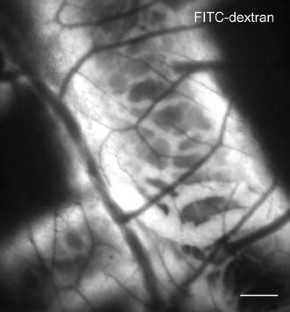

PubMed  CAS  Google Scholar